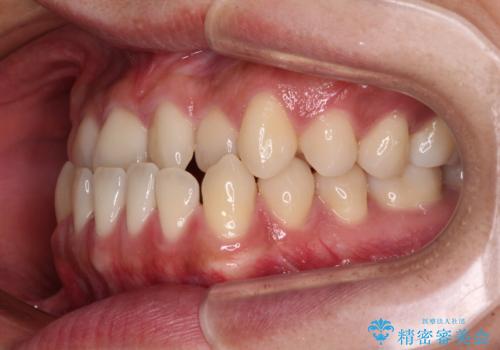

骨格的な左右差も顕著であったため、正中は合わず、上下前歯の一部が接触しない咬み合わせとなることが予想されましたが、正中はもともとのズレが小さかったことから、合わせることができました。

治療期間も10か月間という短期間で終了し、患者様には大変満足していただきました。